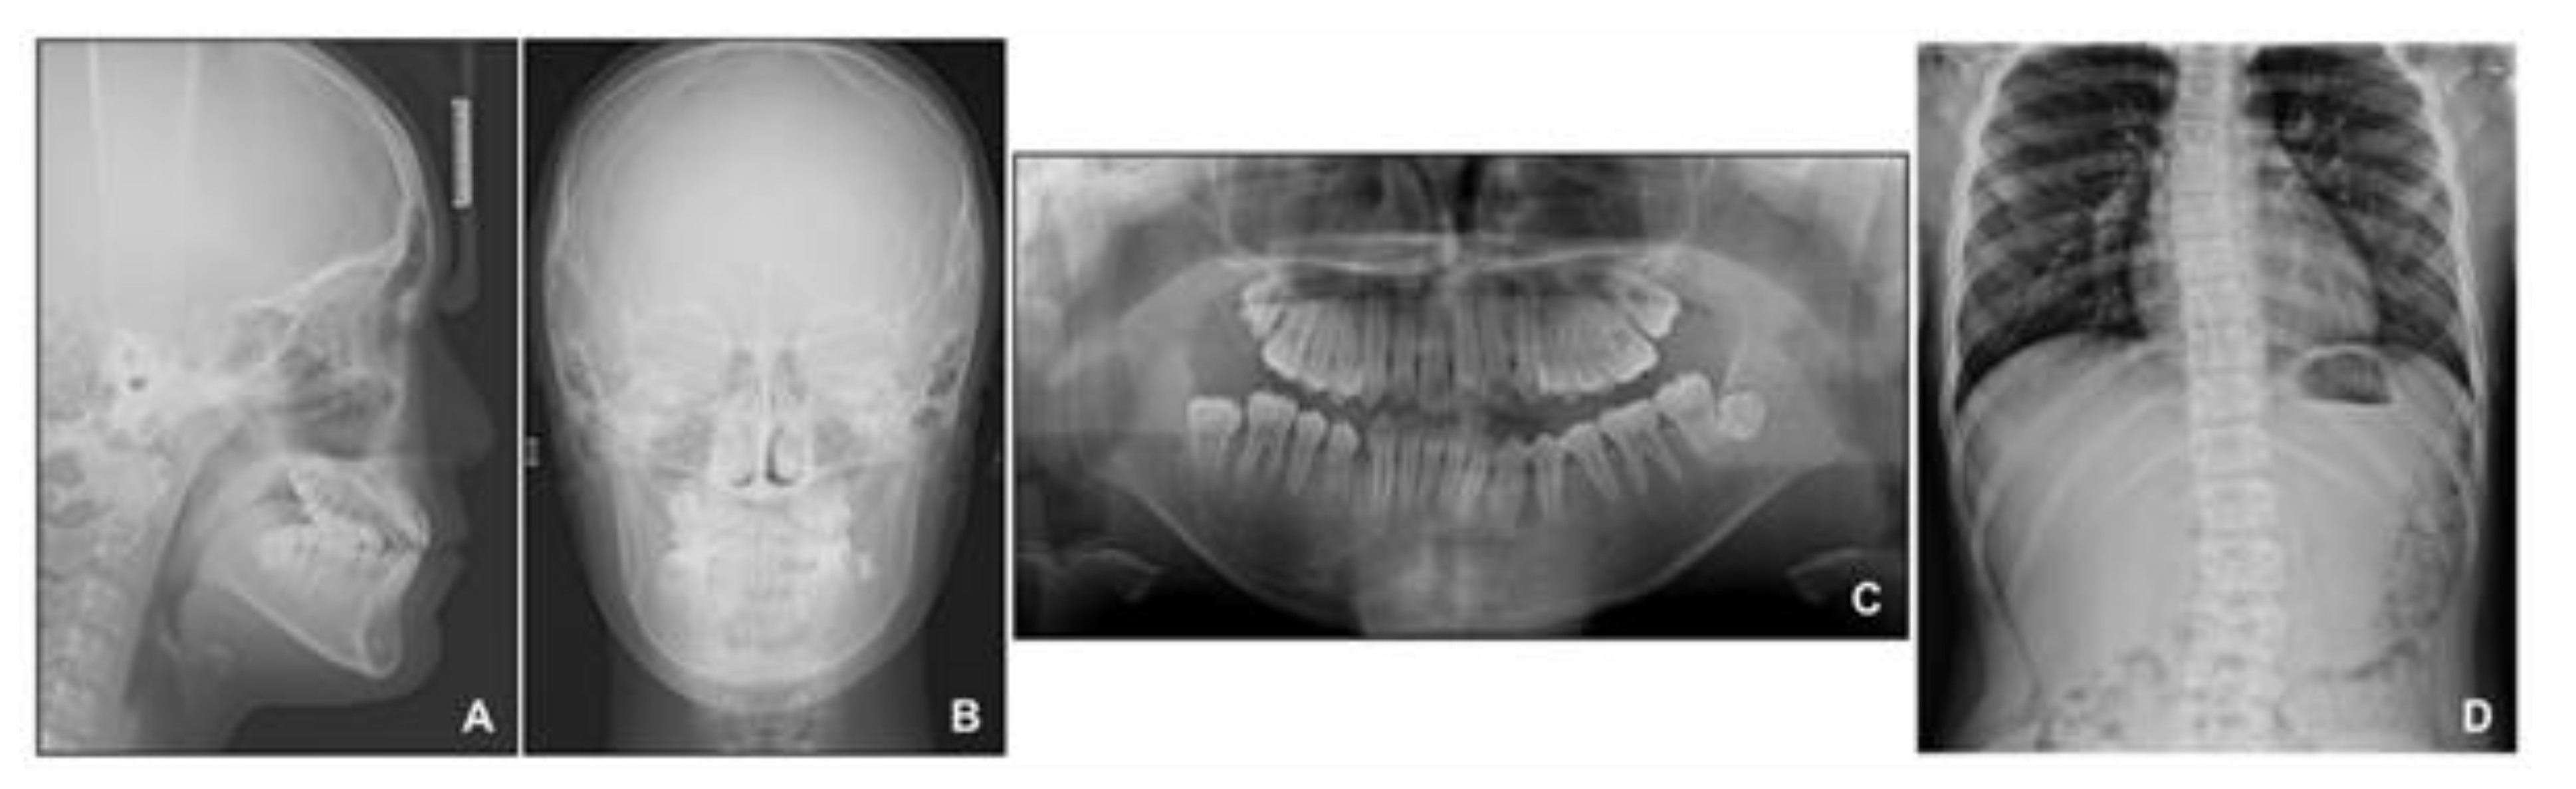

Lateral cephalometric analysis showed an angle of the lines connecting the sella, nasion, and point A (SNA) of 75.4°, an angle of the lines connecting the sella, nasion, and point B (SNB) of 75.7°, and angle of the lines connecting point A, nasion, and point B (ANB) of −0.3° (Table 1 and Figure 3). Both maxillary and mandibular incisors were lingually inclined, and the upper lip was retruded with respect to the Ricketts’ esthetic line. In posteroanterior cephalometric analysis, there were no noticeable asymmetric features. A panoramic radiograph showed that a supernumerary tooth was impacted in the right mandibular premolar area. There were no pathologic osseous findings in the gingival hypertrophic area of the anterior mandible.

Figure 3. Pre-treatment radiographs: (A) Lateral cephalogram; (B) Posteroanterior cephalogram; (C) Panoramic radiograph.